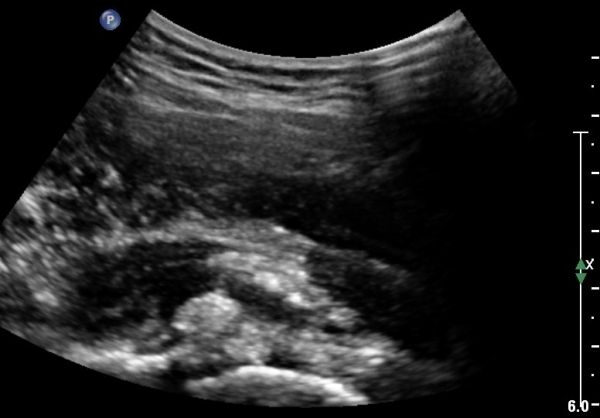

°í°üÀý ¿ÜÃø, ¹Ù·Î µÚ Á¾´Ü¸é°Ë»ç¿Í Ⱦ´Ü¸é °Ë»ç»ó °üÀý ¿Í¼øºÎÀ§¿¡ Ä¿´Ù¶õ °í¿¡ÄÚ ¼®È¸È­°¡ °üÂûµÊ(»çÁø 8, 9)